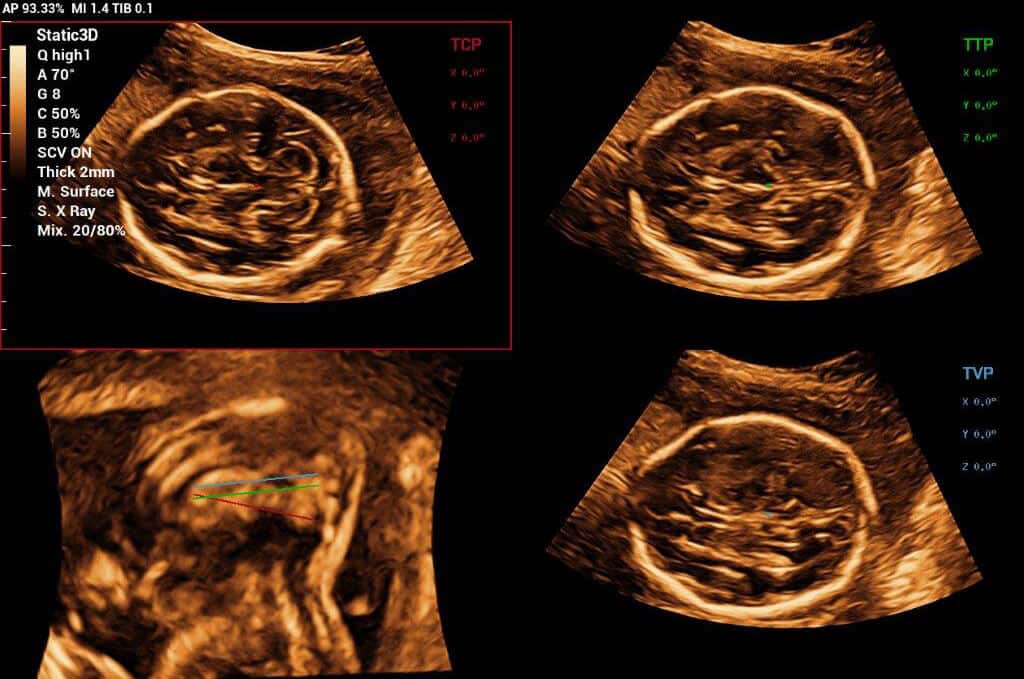

Powered by Mindray’s revolutionary ZONE Sonography (R) Technology+, the Imagyn I9 System boasts advanced ultrasound capabilities and leverages AI-inechanged technologies. The Imagyn I9 starts the process using auto clinical scenario identification, and uses automation at every point, from imaging optimization to planes scenario identification, and uses automation at every point, from imaging optimization to planes acquisition, quantification, and creating an automated workflow. The Imagyn I9 System provides a full-stack smart solution for efficient women’s health, covering wide-ranging applications from pre-pregnancy to obstetric to post-partum.